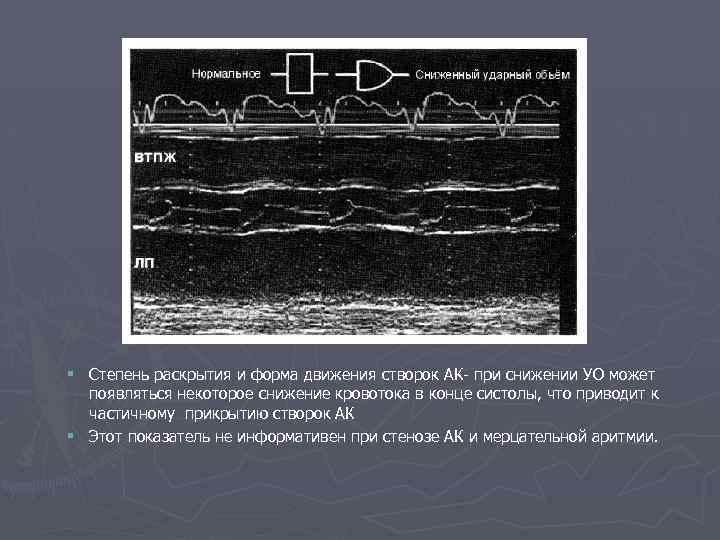

§ Степень раскрытия и форма движения створок АК- при снижении УО может появляться некоторое снижение кровотока в конце систолы, что приводит к частичному прикрытию створок АК § Этот показатель не информативен при стенозе АК и мерцательной аритмии.